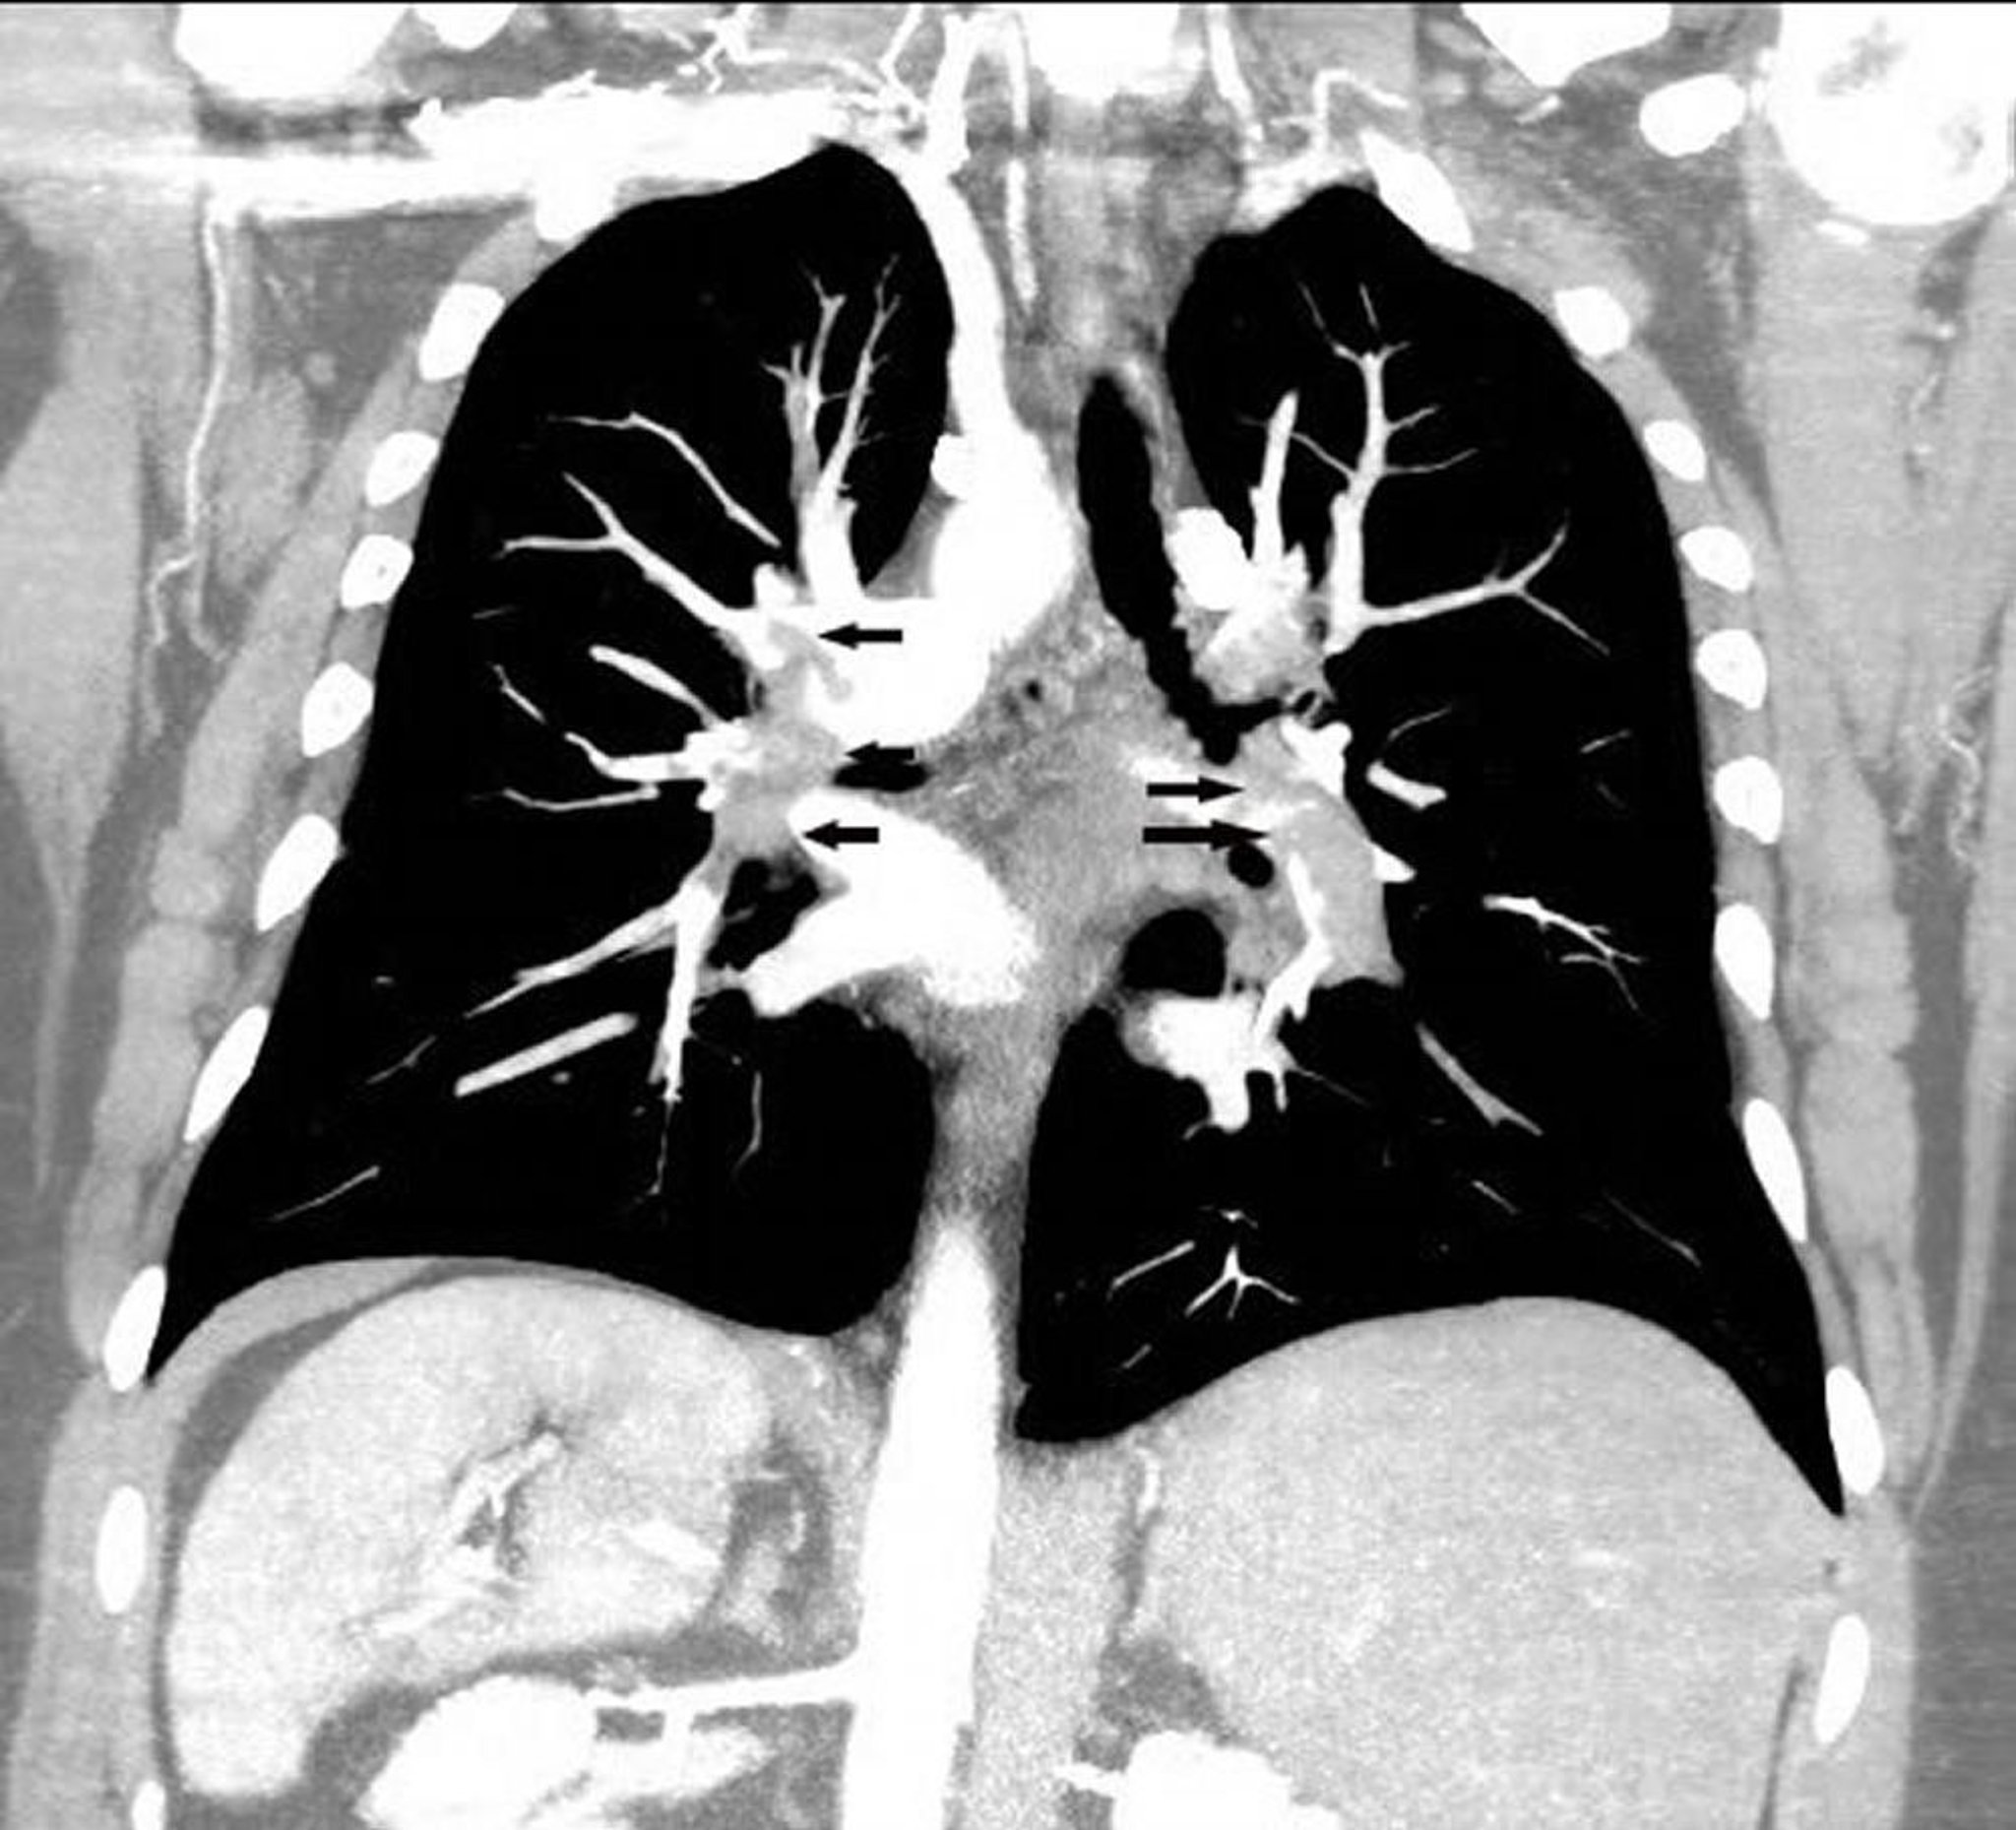

Angiographie pulmonaire par reconstruction TDM coronale

L'angio-TDM pulmonaire de reconstruction coronale montre une embolie pulmonaire étendue et des artères pulmonaires bilatérales (flèches).

Image courtoisie de Hakan Ilaslan, MD.